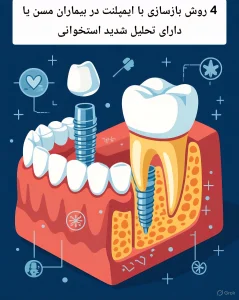

تفاوت مراقبت در بریج دندان طبیعی و ایمپلنتی

| ویژگی | بریج روی دندان طبیعی | بریج روی ایمپلنت |

| خطر پوسیدگی | بالا | ندارد |

| خطر التهاب لثه | متوسط | بالا |

| تحلیل استخوان | کندتر | سریعتر در صورت عفونت |

| حساسیت به پلاک | زیاد | بسیار زیاد |

این جدول نشان میدهد که حذف پلاک در بریجهای دندانی بهویژه در نوع ایمپلنتی، نقش حیاتی در حفظ درمان دارد.